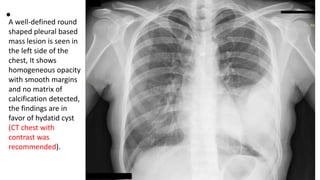

•A well-defined round

shaped pleural based

mass lesion is seen in

the left side of the

chest, It shows

homogeneous opacity

with smooth margins

and no matrix of

calcification detected,

the findings are in

favor of hydatid cyst

(CT chest with

contrast was

recommended).